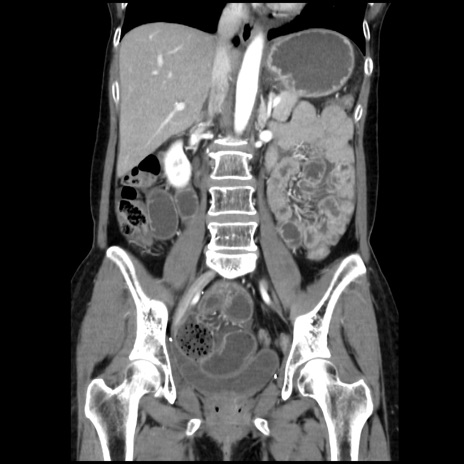

症例32(冠状断像)

【症例】40歳代 女性

【主訴】上腹部痛、嘔気・嘔吐

【現病歴】約9時間前頃から急に上腹部痛、嘔気、嘔吐が出現。改善しないため救急要請。

【既往歴】子宮頚癌(広汎子宮全摘術、放射線療法)、腸閉塞

【身体所見】腹部:平坦、軟、腸雑音亢進、上腹部を中心に腹部全体に圧痛あり。

【データ】WBC 8400、CRP 0.03